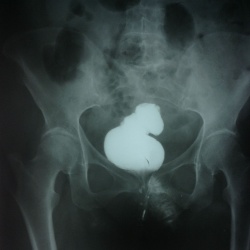

Здравствуйте,пациентке назначена рентгенография Пояснично-кр отд п-ка,1948 гр,случайная находка,что за тень?смещается при повороте